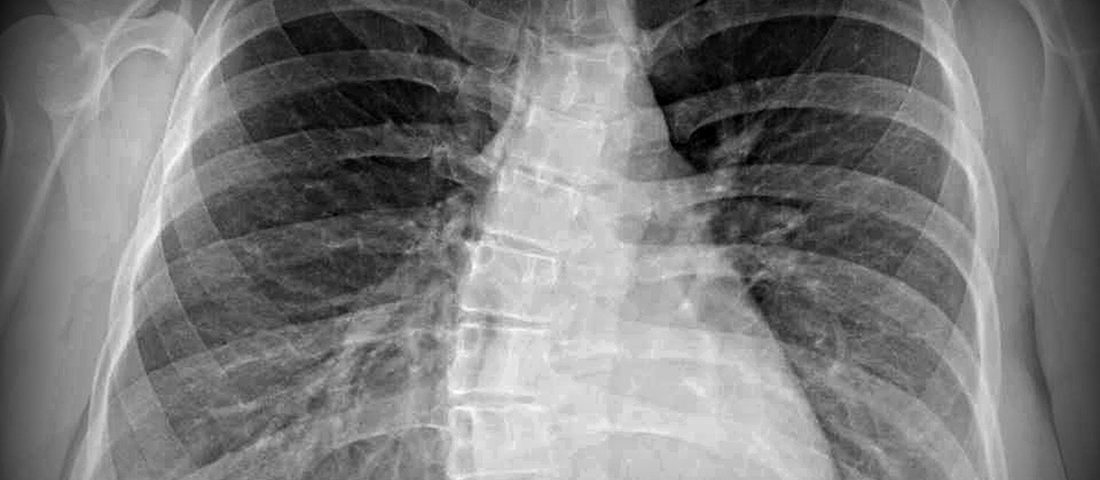

دندهها استخوانهای هلالیشکلی هستند که از اندامهای حیاتی قفسه سینه محافظت میکنند و در عین حال ریهها را قادر میسازند تا برای تسهیل تنفس متورم شوند. هفت جفت اول دندهها که به نام «دندههای حقیقی» شناخته میشوند، به وسیله غضروف مستقیماً به جناغ سینه متصل هستند. پنج جفت بعدی به عنوان «دندههای کاذب» شناخته میشوند که سه جفت از آنها به طور مشترک به جناغ سینه متصل هستند. دو جفت آخر به نام «دندههای شناور» شناخته میشوند، زیرا به جناغ سینه متصل نیستند، بلکه به ستون فقرات متصل هستند.